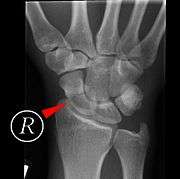

Fracture

Fractures of the scaphoid are the most common of the carpal bone injuries, because of its connections with the two rows of carpal bones.[1] :177

The scaphoid can be slow to heal because of the limited circulation to the bone. Fractures of the scaphoid must be recognized and treated quickly, as prompt treatment by immobilization or surgical fixation increases the likelihood of the bone healing in anatomic alignment, thus avoiding mal-union or non-union. Delays may compromise healing. Failure of the fracture to heal ("non-union") will lead to post-traumatic osteoarthritis of the carpus.[1] :189 One reason for this is because of the "tenuous" blood supply to the proximal segment.[2] Even rapidly immobilized fractures may require surgical treatment, including use of a headless compression screw such as the Herbert screw to bind the two halves together.

Healing of the fracture with a non-anatomic deformity (frequently, a volar flexed "humpback") can also lead to post-traumatic arthritis. Non-unions can result in loss of blood supply to the proximal pole, which can result in avascular necrosis of the proximal segment.